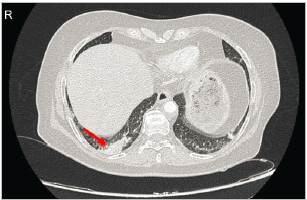

The patient underwent computed tomography (CT) of the chest and abdomen, with contrast. The chest CT showed asymmetric enhancement of the right basal parenchyma and a hypoperfused medial area indicating ipsilateral atelectasis, conclusive for acute PTE in the right posterior basal segmental artery, with an apparent ipsilateral posterior basal infarction (Figure 2).

Figure 2 Axial section of the chest CT with contrast showing an area of right basal hypoperfusion (red arrow), which is conclusive for acute PTE of the right posterior basal segmental artery with apparent right posterior basal infarction.